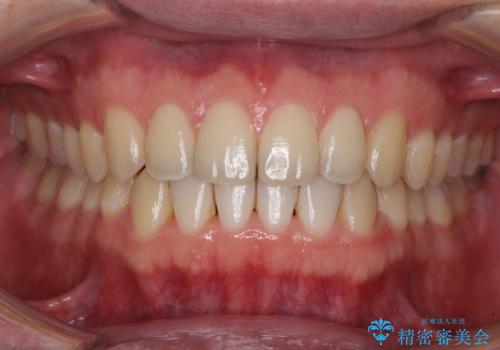

すきっ歯の改善 インビザライン矯正治療

1日22時間の装着時間をしっかりと守ってくださったので、隙間がきれいに閉じ、口元の突出感も改善することができました。